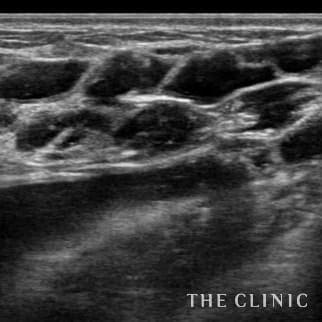

10日前に他院でアクアフィリング豊胸(片胸100ccづつ)を行いましたが、安全性に不安を感じたこと、形や硬さも気に入らないため除去を希望されました。形も悪く、しこりのようになっていました。 エコーをすると乳腺下にアクアフィリングが注入されていましたが、一部は大胸筋内に広がっていました。(写真は乳腺科に見られた大きな塊、黒い部分です。) 処置はエコー下に生理食塩水で溶解して吸引除去でき、無事、形も柔らかさも元に戻りました。治療の概要 アクアフィリング除去+コンデンスリッチ豊胸:乳腺用エコーを用いて、バスト内の状態を確認。その後、生理食塩水でアクアフィリングを溶解する。溶解仕切れない場合には、注射器で吸い出し除去。アクアフィリング の除去後、バストの皮下にコンデンスリッチファット(老化細胞や不純物を取り除いて濃縮させた自己脂肪)を注入。 施術費用 アクアフィリング 除去(会員料金):¥600,000(税込¥660,000)/溶解1部位